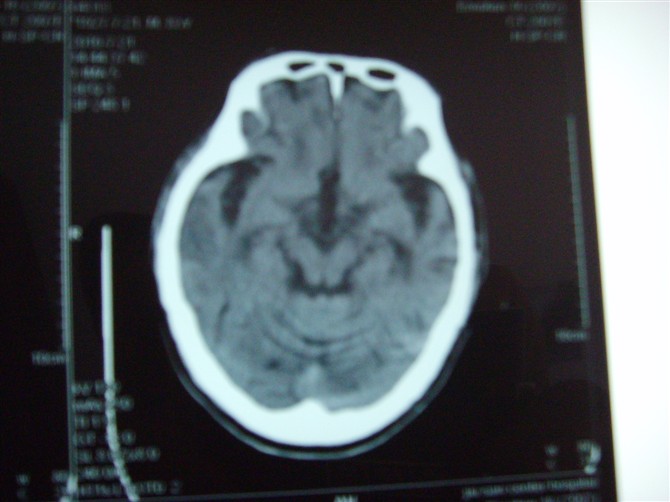

标题: CT27993:男 83岁 头晕伴双下肢无力一天 [打印本页]

标题: CT27993:男 83岁 头晕伴双下肢无力一天

脑萎缩。伴小脑齿状核、苍白球钙化。必要是mri进一步检查。

脑萎缩。伴小脑齿状核、苍白球钙化.脑白质脱髓鞘病变

脑白质变性、脑萎缩。甲状旁腺功能减退。

1)双侧小脑半球脑软化灶。2)全脑萎缩。3)脑白质病。